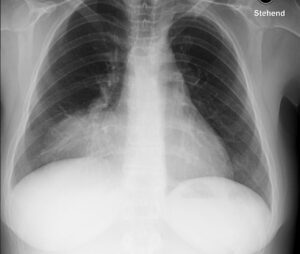

Pneumonie

Eine Mittellappenpneumonie führt zur Aufhebung des rechten Herzrandes, da die entzündliche Infiltration denselben Weichteildichtekontrast wie der rechte Vorhof besitzt.